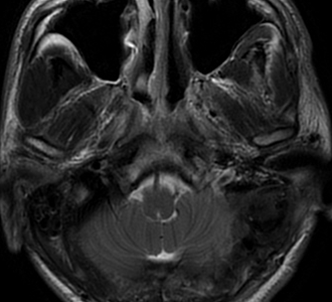

术前影像

入院后行术前检查,核磁共振显示:斜坡偏左占位,脑膜瘤可能性大。

左侧斜坡脑膜瘤